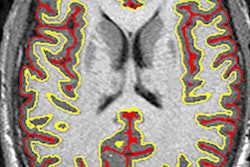

To evaluate the symptoms, clinicians generally turn to diffusion-weighted MR imaging (DWI-MRI) to determine demyelination, which is the erosion of the myelin sheath that protects nerve fibers and nerve impulses.